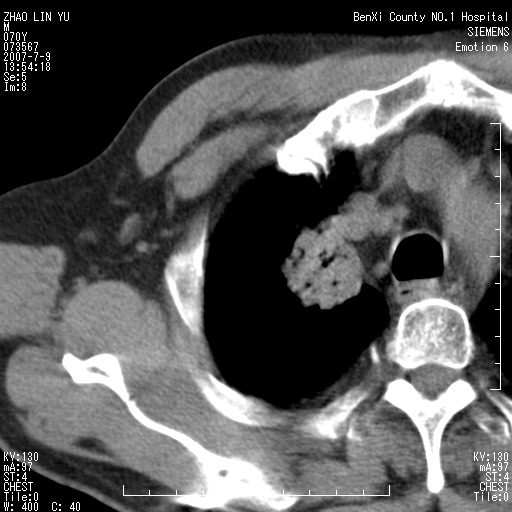

以下是引用王靖旗在2007-7-10 17:12:00的发言:[br] 男、70、咳嗽两个月,半年前换瓣手术,胸片未见异常,于昨天行x片发现右肺上野大片影,行ct扫描,这里是减薄图像,余肺正常。明天晚上会有增强扫描片,到时我会上传。[br][br] 冠状位请大家细看,应该是有意义的,[br][br] 请大家先看平扫发表意见。[br][br]

[br]冠状面[br]

以下是引用zhangzhongshou在2007-7-10 21:43:00的发言:[br]右肺上叶周围型肺癌,以孤立型细支气管肺泡癌可能性大。